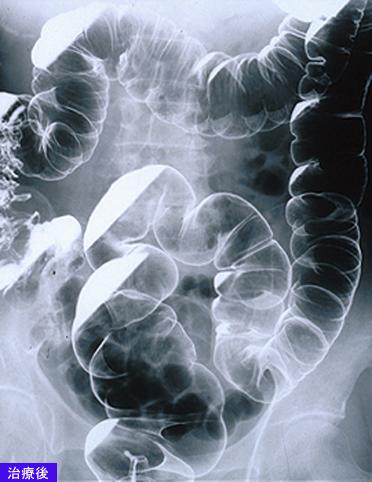

A case of MLP (multiple Lymphomatous Polyposis) type malignant lymphoma which involved the G1 tract including the esophagus.

Malignant Lymphoma/MLP type

Large intestine(Colon)/More than one of the above

X-ray